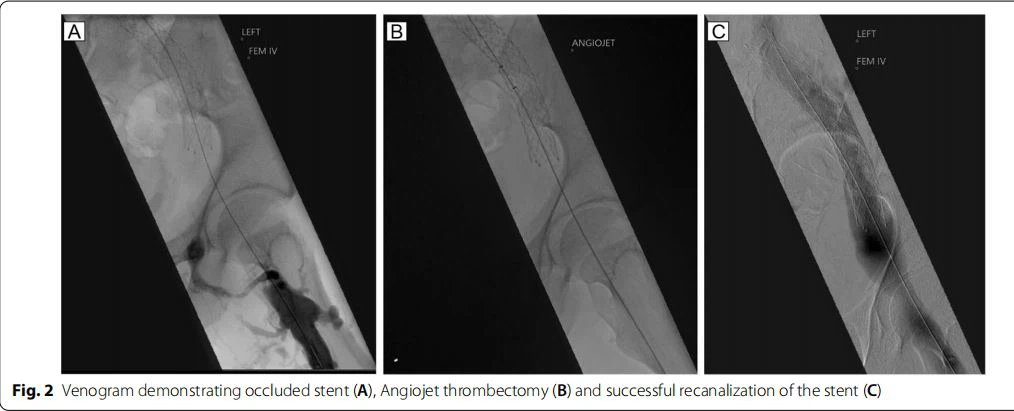

Un varón caucásico de 29-años de edad con una malformación venosa sintomática (VM) conocida en el flanco izquierdo (Fig. 1) ingresó con un historial de 2-días de dolor en la pierna izquierda, hinchazón y decoloración secundaria a TVP. . No había antecedentes de dolor torácico, dificultad para respirar o palpitaciones. Un año antes se le había colocado un stent en la vena ilíaca común izquierda por una lesión de la vena ilíaca no trombótica, para desviar el retorno venoso de la VM. Como permaneció sintomático después de este procedimiento, se realizó una escisión quirúrgica electiva y ligadura del vaso alimentador principal a la VM tres semanas antes de esta presentación. El sangrado en el momento de esta operación obligó a suspender el tratamiento con Apixabán, que estaba tomando anteriormente. No tenía otros antecedentes médicos, incluidos antecedentes conocidos de insuficiencia renal, ni antecedentes familiares deenfermedad renal. En el momento de la presentación, el examen cardiorrespiratorio fue normal. El examen del abdomen reveló una masa firme y palpable en la pared abdominal izquierda, compatible con la VM conocida. La parte superior de la pierna izquierda estaba hinchada con manchas en la piel, pero por lo demás blanda y sin dolor, y los pulsos periféricos estaban intactos. Se iniciaron 7500 unidades dos veces al día de heparina de bajo peso molecular (HBPM) en el momento de la presentación. Después de la venografía por TC (Fig. 1) y la ecografía dúplex, que identificaron un stent venoso ocluido, el equipo de cirugía vascular realizó una trombectomía con angiojet y una venoplastia bajo anestesia general (Fig. 2). Los marcadores de coagulación preoperatorios estaban todos dentro de los límites normales (INR 1.1, APTR 1.1). Intraoperatoriamente, se administraron 8000 unidades de heparina no fraccionada, seguidas de 15000 unidades de HBPM una hora después del procedimiento. Se logró la recanalización exitosa del stent trombosado. En el postoperatorio desarrolló bradicardia y vómitos y fue tratado con antieméticos y líquidos intravenosos. Los vómitos se calmaron después de 36 horas. Permaneció hemodinámicamente estable en todo momento. Tras la intervención quirúrgica se inició una infusión intravenosa continua de heparina para evitar la reoclusión del stent.